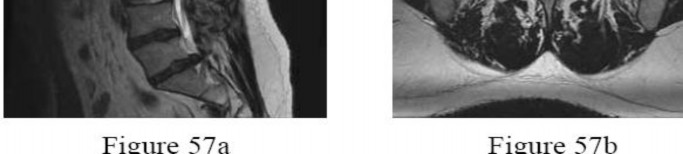

Question 57

Which of the following congenital spinal anomalies carries the highest risk of rapid curve progression and invariably requires early surgical intervention?

Explanation